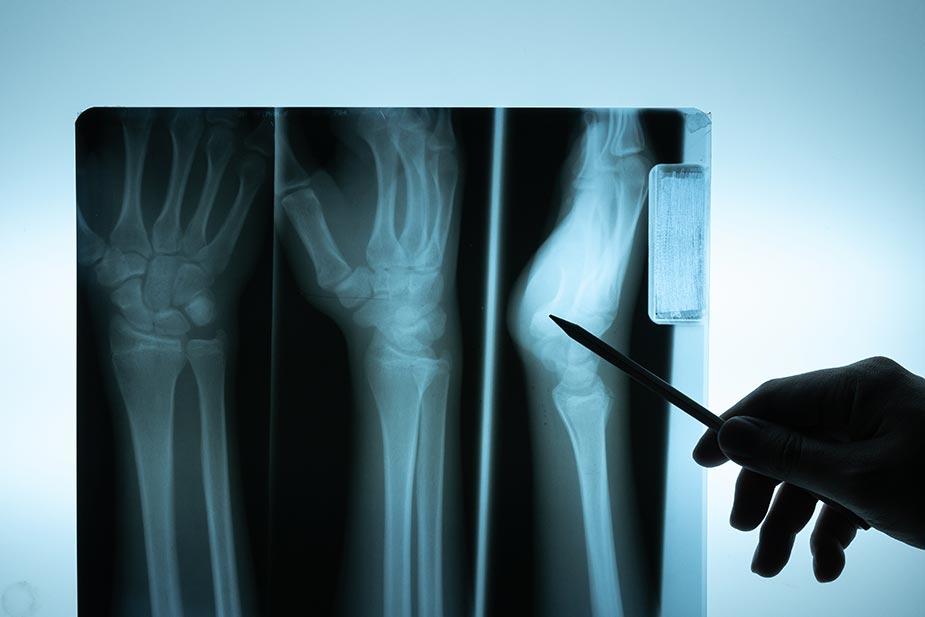

Klasični rendgen je osnovni metod radiološke dijagnostike, koji je zasnovan na primeni X-zraka radi dobijanja slike različitih segmenata ljudskog tela. Predstavlja bezbolnu, neinvazivnu i preciznu metodu. Glavne prednosti rendgena jesu brzina snimanja i postavljanje tačnih dijagnoza.

Radiografija se obavlja radi ispitivanja koštano-zglobnog sistema i treba je raditi kada postoji povreda kostiju sa sumnjom na njihov prelom, prilikom iščašenja zgloba ili njihovog deformiteta, kada se oseti bol u određenim delovima tela (rukama, nogama, glavi, grudima, stomaku…).

Ova metoda brzo i jednostavno pruža informacije o zapaljenskim bolestima kostiju ili njihovim povredama, tumorima i cistama koštano-zglobnog sistema, kao i drugim deformitetima bilo da su stečeni ili urođeni.

Rendgenski snimak se koristi za otkrivanje preloma i iščašenja kostiju, kao i za otkriće upale pluća i malignih bolesti. S druge strane, CT skener je vrsta naprednog rendgenskog aparata kojim se preciznije dijagnostifikuju stanja unutrašnjih organa, a zajedničkom primenom skenera i rendgena dobijaju se pravi rezultati.

Slike proizvedene rendgenskim zracima su u 2D formatu, dok se 3D slike formiraju tokom CT skeniranja.